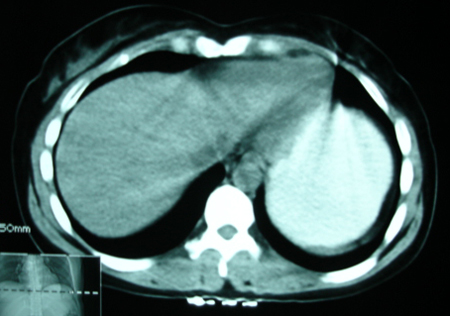

以下是引用bmw011在2009-4-23 13:28:00的发言:[br]考虑右肾包膜下血肿。

以下是引用卜一在2009-4-23 15:43:00的发言:[br]考虑右肾包膜下血肿,不排除占位病变伴出血可能,建议进一步检查。